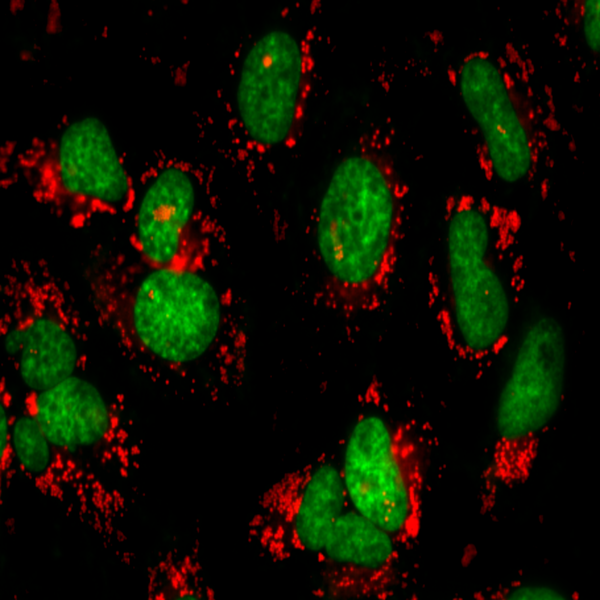

- General and specialized tissue and cell staining

- Immunocytochemistry (ICC) technique

- Immunohistochemistry (IHC) technique